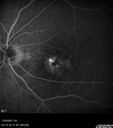

Conversion to Wet AMD after Izervay32 views83 year old man whose left eye had minimal GA and converted from dry to wet AMD after a single Izervay treatment

Conversion to Wet AMD after Izervay31 views83 year old man whose left eye had minimal GA and converted from dry to wet AMD after a single Izervay treatment

Conversion to Wet AMD after Izervay30 views83 year old man whose left eye had minimal GA and converted from dry to wet AMD after a single Izervay treatment

Conversion to Wet AMD after Izervay29 views83 year old man whose left eye had minimal GA and converted from dry to wet AMD after a single Izervay treatment

Conversion to Wet AMD after Izervay28 views83 year old man whose left eye had minimal GA and converted from dry to wet AMD after a single Izervay treatment

Conversion to Wet AMD after Izervay27 views83 year old man whose left eye had minimal GA and converted from dry to wet AMD after a single Izervay treatment

Conversion to Wet AMD after Izervay26 views83 year old man whose left eye had minimal GA and converted from dry to wet AMD after a single Izervay treatment

Conversion to Wet AMD after Izervay25 views83 year old man whose left eye had minimal GA and converted from dry to wet AMD after a single Izervay treatment

Conversion to Wet AMD after Izervay24 views83 year old man whose left eye had minimal GA and converted from dry to wet AMD after a single Izervay treatment